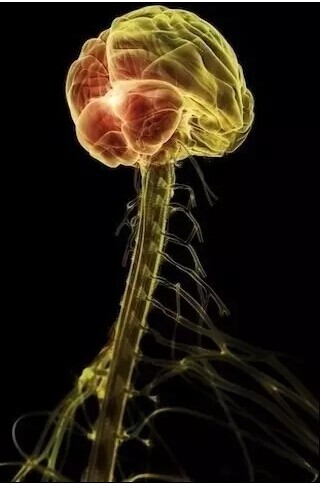

大脑

颈椎、大脑